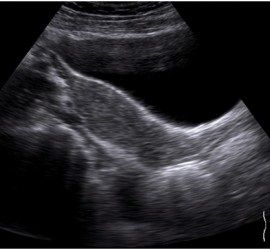

Ultrasound-based transient elastography provides excellent diagnostic accuracy in identifying cirrhosis due to recurrent hepatitis C following liver transplantation.